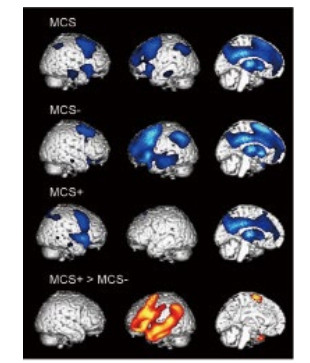

2.1 神经影像 2.1.1 正电子发射型计算机断层显像(positron emission computed tomography,PET)PET是最早应用于意识障碍临床研究的影像技术之一[24-25]。其实质是分子生物学与医学影像学的相互交叉融合,运用标记后的葡萄糖来反映局部脑组织功能。临床研究表明,觉知的损伤和一些特定脑区葡萄糖的摄取量降低有关,如一些联络皮质[26]、两侧丘脑等[27]。利用PET技术,还可以进一步区分一些意识障碍的亚型。如MCS临床可以细分为“MCS+”与“MCS-”,前者的意识水平稍好,可以理解一些语言,并能完成简单的指令动作。PET的对比研究发现,与MCS-患者相比,MCS+患者在语言理解的相关脑区还保留一定的代谢活性[28](图 2)。

| 图 2 PET下MCS-患者与MCS+患者图像 |